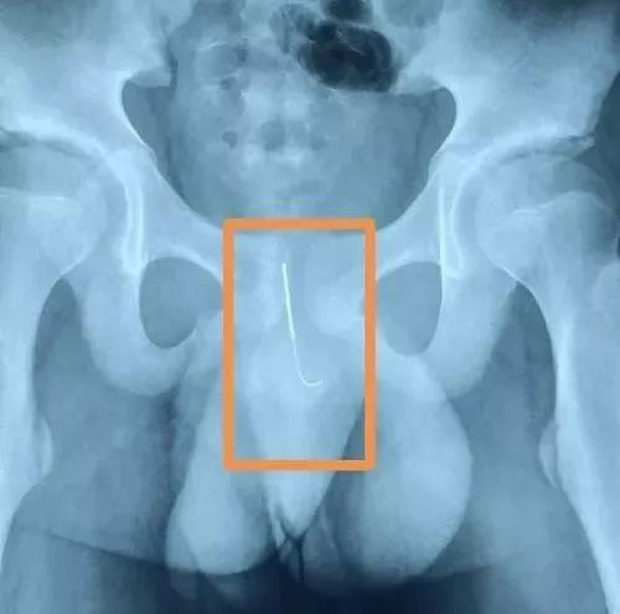

Hình ảnh chụp X quang cho thấy chiếc kim nằm trong dương vật của cậu bé.

Cây kim châm cứu dài 11cm được lấy ra từ dương vật cậu bé.